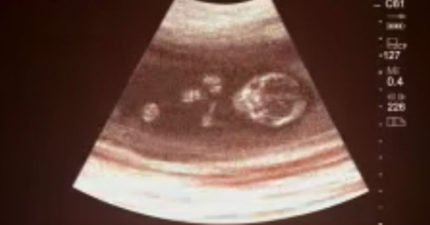

13歲媽媽到醫院「墮胎成功」,但幾週後醫生「一看超音波」才發現了最不可能的奇蹟!

June 26, 2016

世界